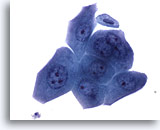

Urine, échantillon négatif

Les cellules urothéliales peuvent être rondes et mononucléaires, comme sur les figures 6 à 8.

20x

Urine, échantillon négatif

Les cellules urothéliales peuvent être rondes et mononucléaires, comme sur les figures 6 à 8.

20x